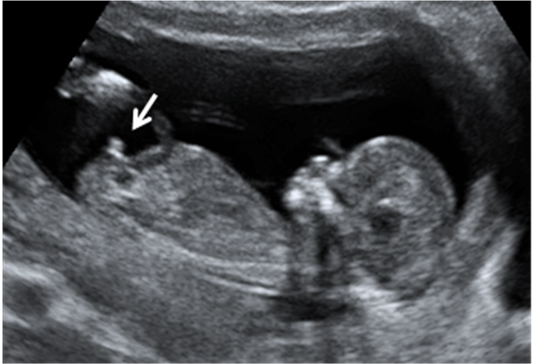

El cordón umbilical es una estructura gelatinosa que suele enrollarse alrededor del feto a medida que este se mueve, especialmente en el primer y segundo trimestre de embarazo. Son perfectamente visibles en las ecografías en 3D.

Feto con cordón umbilical enrollado al cuerpo

Vemos la imagen en tres dimensiones de un feto de 13 semanas de gestación. El cordón umbilical (indicado por las flechas) se asemeja un cinturón de seguridad, ya que pasa del hombro izquierdo a cadera derecha. Luego el cordón continúa por debajo de las piernas para insertarse en el ombligo del bebé.